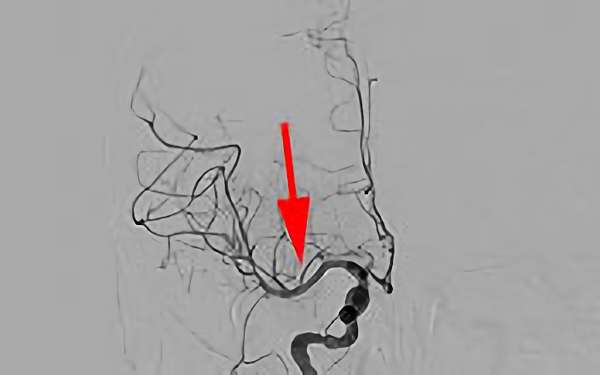

No.800 手術中